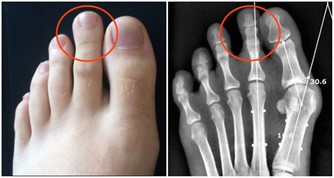

6、有助於淋巴系統

大部分的人都很少會去在意自己位於頸部、腋下等部位的淋巴結,但其實它們對於身體健康是非常重要的!主導淋巴管的就是身體的左側,所以如果你睡在這邊就可以讓身體有更多的時間來過濾毒素!